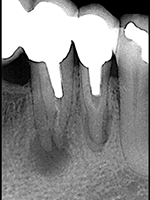

A la radiographie, le kyste se présente commeune tache ronde et sombre à la base des racines.